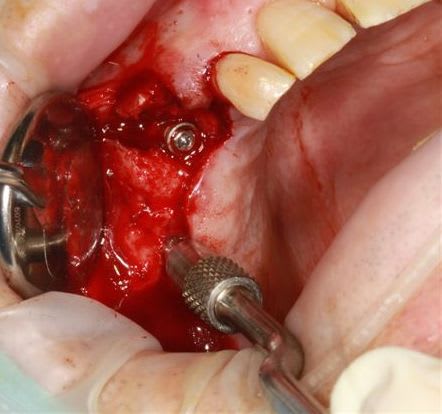

modelage zone 13,finitions, mise en place du bloc osseux, qui sera soigneusement impacté (pas de vis) prélèvement d'un petit bloc triangulaire pour finir la fermeture, éponges de gelatemp, sutures.